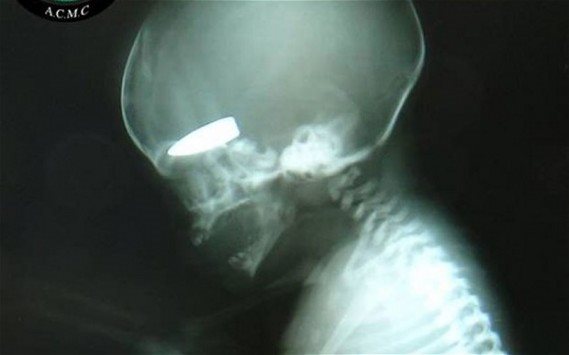

ΣΟΚ από Συρία! Έμβρυο με σφαίρα στο κρανίο!!

Έγκυες γυναίκες είναι στόχοι ελεύθερων σκοπευτών στη Συρία και μάλιστα “επιβραβεύονται” μ΄ αυτό με μερικά πακέτα τσιγάρα. Η αποκάλυψη που δημοσιεύεται στην βρετανική εφημερίδα Telegraph, είναι ανατριχιαστική και συνοδεύεται από τη φωτογραφία ενός εμβρυου στο οποίο έχει “καρφωθεί” η σφαίρα ενός ελεύθερου σκοπευτή.

Το ρεπορτάζ της εφημερίδας υποστηρίζει ότι αυτές τις βολές τις κάνουν ελέυθερεοι σκοπευτές του Άσαντ οι οποίοι έχουν λάβει σχετικές εντολές να “προτιμούν” ως στόχους τις έγκυες γυναίκες. Και για κάθε τέτοιο στόχο αμείβονται με μερικά πακέτα τσιγάρα!

Σε μία μόνο ημέρα περισσότερες από έξι έγκυες γυναίκες είχαν χτυπηθεί από πυρά ελεύθερων σκοπευτών. Οι περισσότερες επιβίωσαν όχι όμως και τα έμβρυα.

Η βρετανική εφημερίδα δημοσιεύει τη φωτογραφία της ακτινογραφίας που δείχνει ένα έμβρυο να έχει σφηνωμένο στο κρανίο του μια σφαίρα . onalert